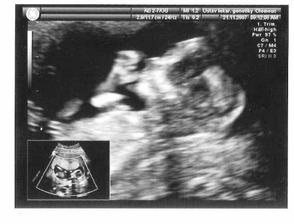

Někdy z jara jsme se s manželem rozhoupali (tedy to rozhoupání bylo spíš na mě, manžel chtěl už dřív:o) a rozhodli se pro miminko. Zvážili jsme všechna pro a proti a došli jsme k závěru, že ta nejvhodnější doba nebude nikdy. Takže nač čekat a po necelých 4.měsících se nám zadařilo a 28. května 2008 se nám narodí potomek-naše mláďátko:o)